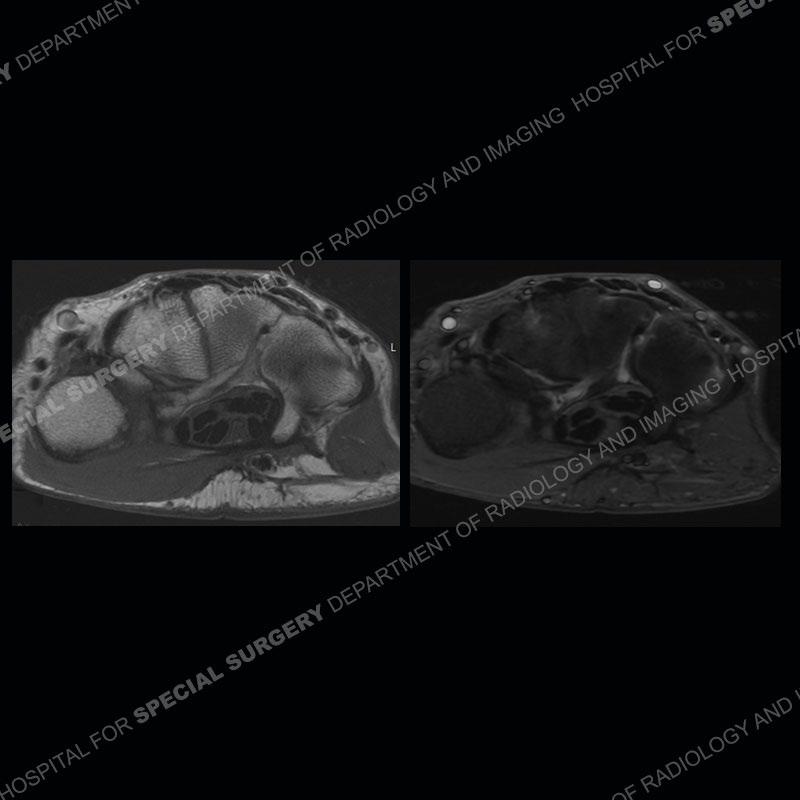

The radiographs in this case are not particularly contributory. The MRI demonstrates tenosynovitis of the first extensor compartment manifest by fluid/synovitis distention of the tendon sheaths. Multiple tendon slips are present of the abductor pollicis longus (APL) and with severe tendinosis seen of one of the tendon slips. Other areas of slightly increased signal and tendinosis are present of the components of the APL. Noted is a somewhat prominent septum separating the more dorsal extensor pollicis brevis (EPB) from the APL.

This case in particular highlights some of the normal variants of the first extensor compartment which can be confusing as well as clinically important. The APL can have multiple tendon slips with the insertion mostly being to the base of the thumb metacarpal but with additional insertions found of the trapezium and occasionally other thenar muscles. With additional tendinosis and partial tearing, this can become particularly confusing.

There can also be a partial or complete septum between the APL and EPB. This can particularly come into play with injections and positioning the needle into both sub-compartments to ensure that both tendons are bathed in the injectate.